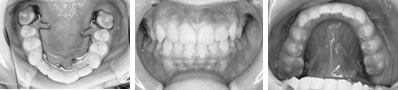

併用した長期経過症例 4歳

治療開始時年齢は6歳半でしたが、永久歯は1本もありませんでした。右上の乳歯Dから左上の乳歯Cまでが反対咬合の状況でした。

レントゲンの検査、家族暦などから骨格的な下顎前突の程度が大きいことがわかりましたので、オトガイ帽装置(チンキャップ)を使用することになりました。

この装置の使用効果についてはさまざまな論拠、発表がありますが、本院では直接的に下顎骨を小さくする効果は無いと考えています。しかしながら、他の装置の使用効果を高めたり、習癖を除去する効果があり、その結果上顎の本来の成長が得られて上下顎の大きさのバランス改善が得られると思われます。少しでも治療を楽しむため色付の装置も用意しています。